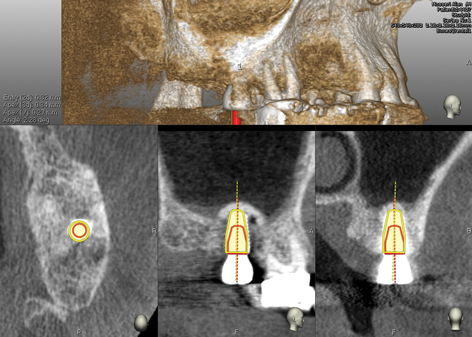

Fig 12. CBCT of final implant placement with

cross-section of maxillary left side sinus elevation.

Figure 12

Upon completion of the surgery a postoperative CBCT was taken to evaluate the sinus membrane and ensure integrity. The navigational unit's software was used to determine accuracy of the planned implant position versus the surgical outcome (Figure 7). A small deviation consisting of 0.32 mm on entry, 0.34 mm at apex, and angle of 2.28 degrees was observed. The postoperative period was uneventful.

Fig 7. Evaluation of implant placement and sinus elevation with

navigational unit software by superimposing pre- and postoperative

CBCT plan and surgical outcome.

Figure 7